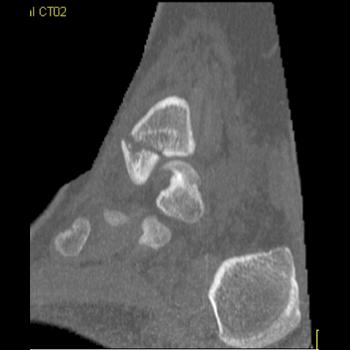

Clinical History: 12 year old female who fell down steps. She presents with left lower extremity pain.

CT Findings: Nondisplaced triplane left ankle fracture involving medial malleolus, with opened epiphysis.

Diagnosis: Minimally displaced of the medial malleolus and widening of the epiphyseal plate defined.

Outcome: Nonweightbearing. She was placed in a splint.